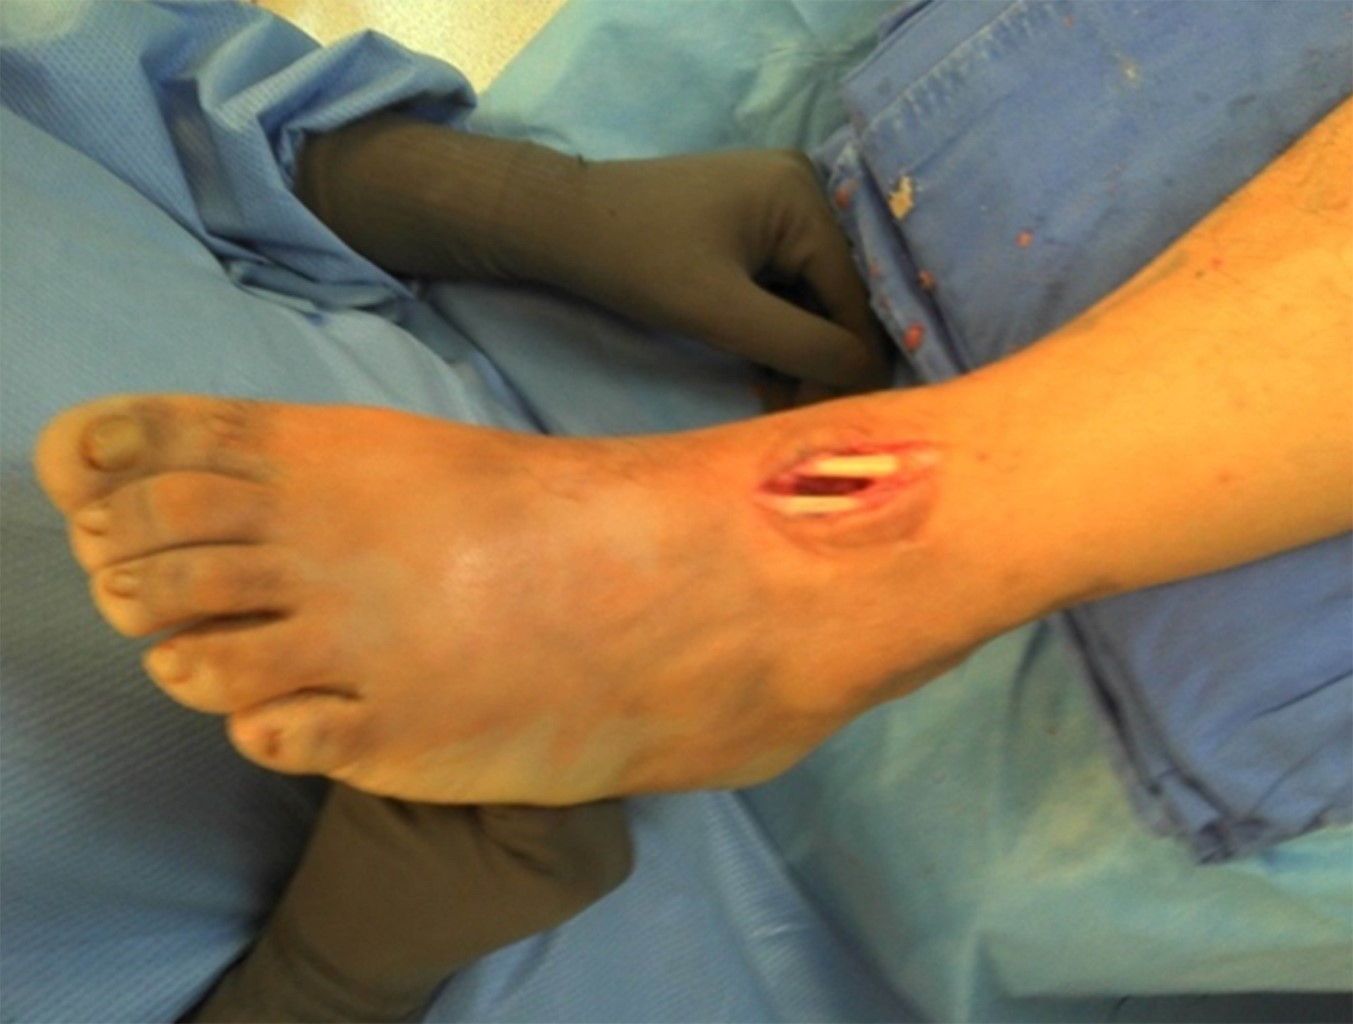

Se realiza un abordaje anterior de 2 a 3 cm a nivel de la articulación tibioastragalina del tobillo, se diseca por planos y se tiene que tomar como referencia el tendón del tibial anterior y el tendón extensor común de los dedos así como cuidar el paquete vascular y entrar entre ambos tendones (Figura 1); se realiza resección de hueso esclerótico con fresa mínima invasiva y se efectúan múltiples perforaciones para obtener un lecho sangrante conservando ambos maléolos.

Se continúa con la incisión plantar para el orificio de entrada del clavo retrógrado, introducción del clavo guía, tomando como referencia el eje de la tuberosidad anterior de la tibia y el segundo rayo y se verifica la dirección mediante intensificador de imágenes. Se realiza fresado retrógrado del canal para la introducción del clavo, longitud 140 × 10 mm, (se utilizó el mismo clavo centromedular en todos los pacientes, diseñado en el servicio de deformidades neuromusculares) (Figura 2).

Figura 1